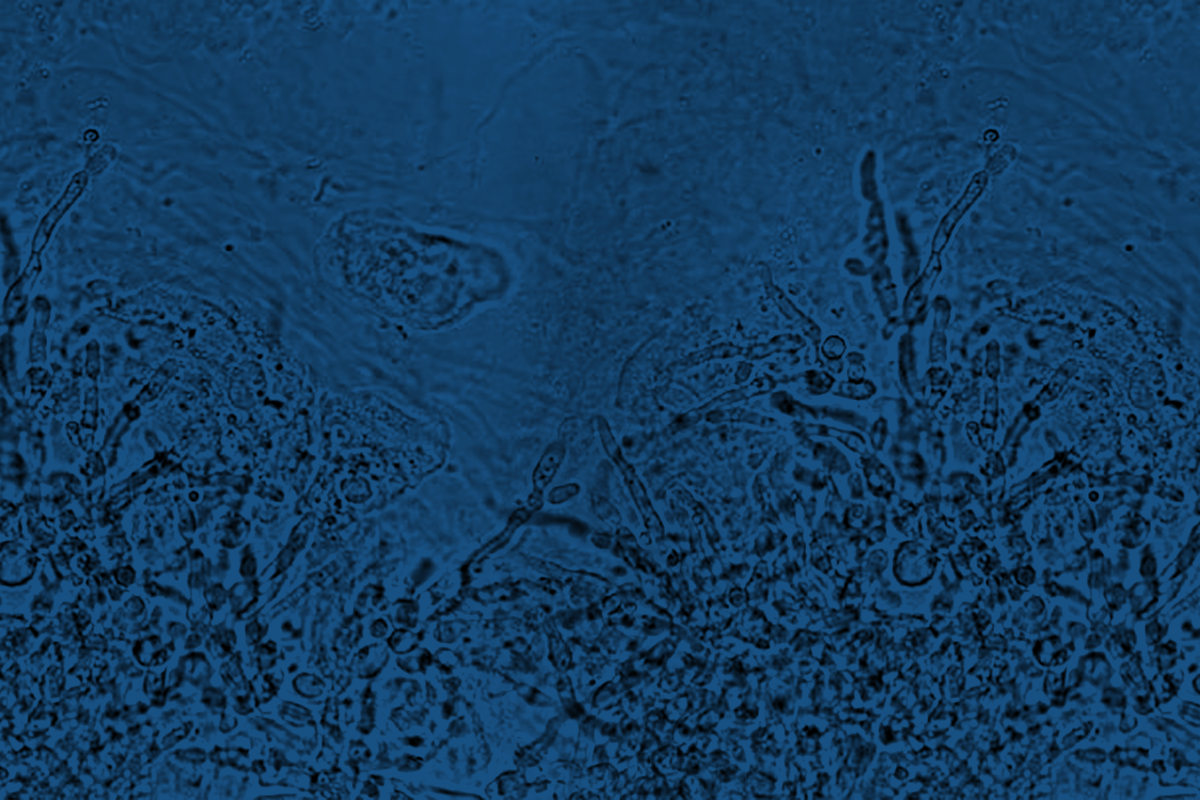

Гонорея — бактериальная инфекция, передаваемая половым путем. Ежегодно в мире гонореей заболевает более 75 миллионов человек. Возбудитель гонореи — Neisseria gonorrhoeae поражает слизистые половых путей, прямой кишки, конъюнктивы глаз и ротоглотки. Это серьезное заболевание, приводящее к осложнениям в виде хронических воспалительных процессов в половых путях, импотенции, бесплодия, невынашивания беременности и др. До недавнего времени это заболевание вполне успешно излечивалось, однако последние годы все чаще сообщалось, что бесконтрольное назначение антибактериальной терапии, в том числе для профилактики заражения, приводит к увеличению доли резистентных штаммов возбудителя. С 2016 года ВОЗ рекомендует для терапии гонореи использовать комбинацию препаратов — азитромицин + цефтриаксон. Выявление случаев широкой устойчивости Neisseria gonorrhoeae к антибиотикам, включая оба препарата первой линии терапии, подводит определенную черту в эпохе эффективного лечения заболевания. В текущей ситуации, без ответных мер надлежащего контроля за распространением устойчивых штаммов, адекватной антибактериальной терапии заболевания, эффективных профилактических мер, гонорея, впервые за более, чем 80 лет, вновь может стать неизлечимым заболеванием.